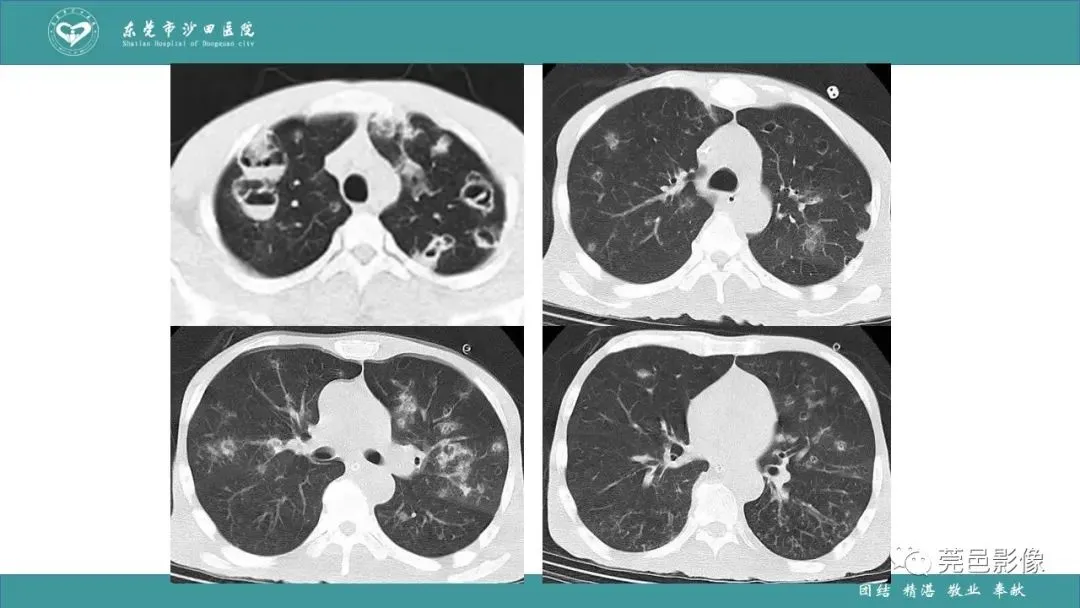

>课件 | 肺炎克雷伯杆菌肺炎影像学诊断与鉴别诊断

课件 | 肺炎克雷伯杆菌肺炎影像学诊断与鉴别诊断